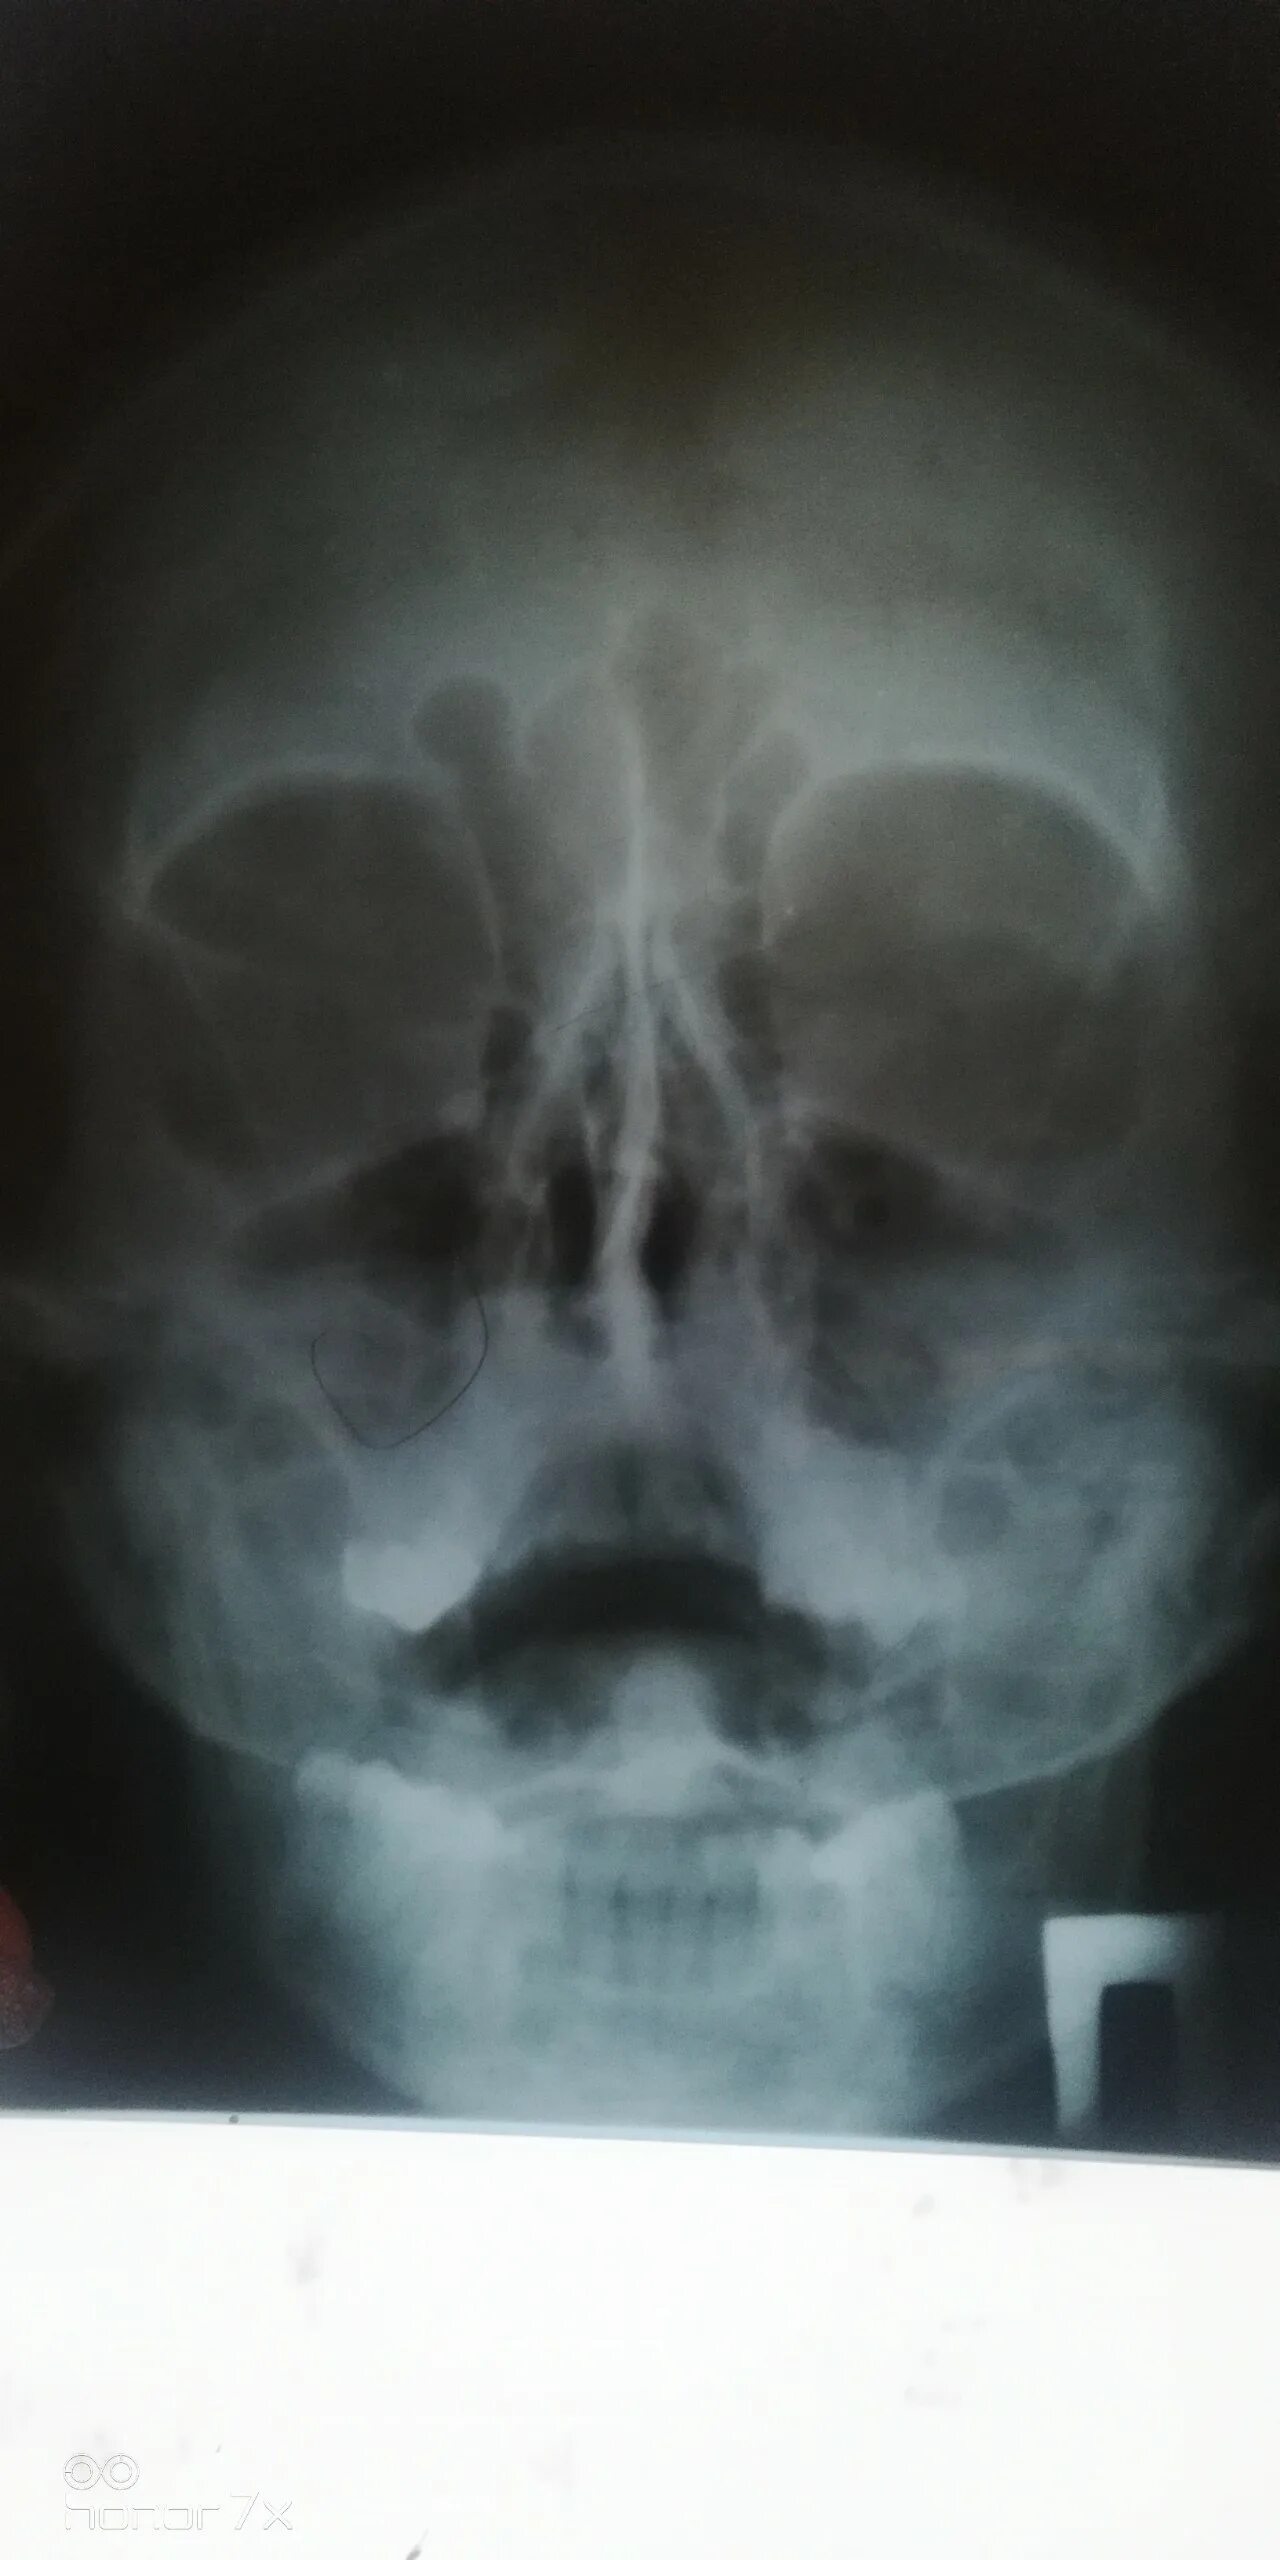

Как выглядит гайморит в носу